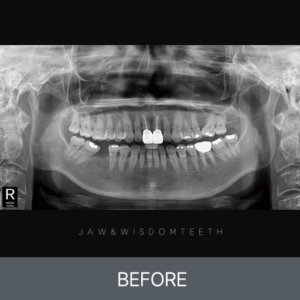

사랑니 CASE